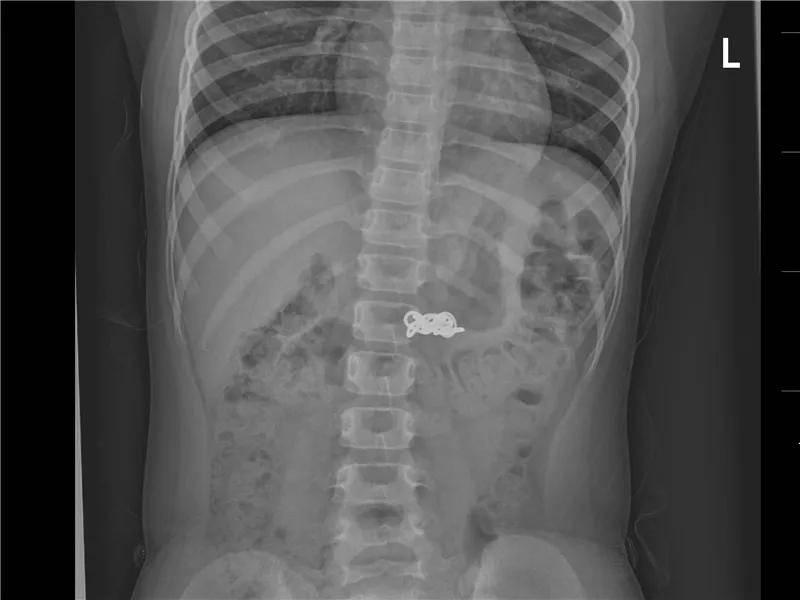

6岁·磁力珠

5小时前不慎误服磁力珠,未见呕吐,无腹痛。